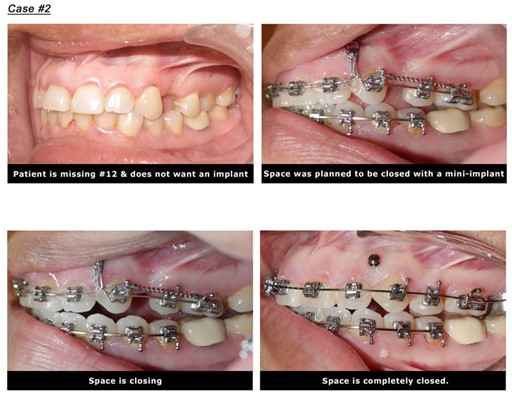

4. Close the space of a missing tooth.

Missing teeth are associated with a different degree of bone loss. This bone loss will place a challenge to replace the missing tooth with a traditional dental implant. Another alternative to the dental implant is to close the space with braces if enough teeth exist. This technique will require the use of a Temporary anchorage device TADS to direct the force into the direction of the missing tooth. Make sure the root size of the moving tooth is strong enough “conical roots in molars perform weakly in bodily movement”